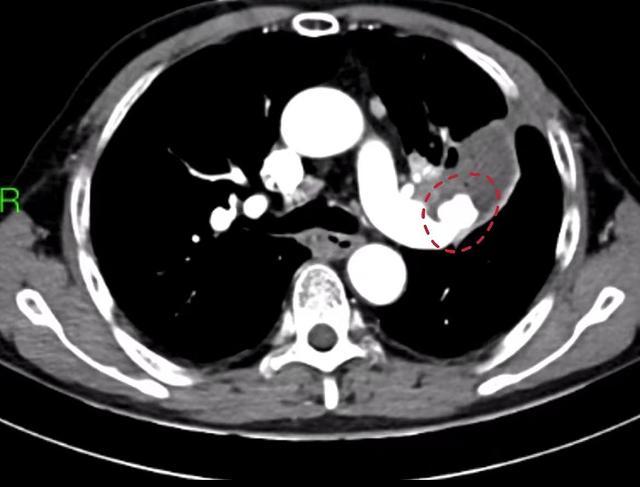

▲术前胸部CT显示患者出现左下肺动脉假性动脉瘤(红圈内)

由于患者病情危急,瘤体随时可能破裂再次发生大咯血。湖南省人民医院胸外科学科主任佘科霖立即组织团队详细评估患者病情,通过反复讨论后决定为患者实施急诊手术。